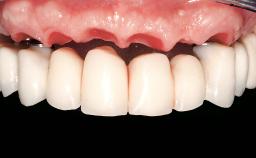

Immediate Loading of Eight Implants in the Maxilla and Six Implants in the Mandible and Final Restoration with Three-Unit and Four-Unit FDPs

Extensive scientific evidence has confirmed that immediately loaded implants with fixed full-arch provisional restorations can osseointegrate with success rates similar to conventionally or delayed loaded implants. A number of immediate-provisionalization techniques for edentulous jaws have been described. Some protocols differ when it comes to prefabricated provisional templates versus complete denture conversion; intrasurgical impressions versus direct relining; and cemented versus screw-retained provisional restorations. In this context, complete-denture conversion has been proposed for either intrasurgical impressions or direct relining. Another possibility is the utilization of a prefabricated provisional to be adapted either in the mouth (by direct relining) or in the laboratory (on a working model obtained from an intrasurgical impression).

Prosthesis Type FDP

Defining Characteristics Fully edentulous upper jaw to be rehabilitated with an implant-borne fixed dental prosthesis

Loading Protocol Immediate

Occlusal Scheme/Issues Anterior guidance